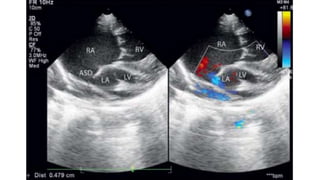

ECHOCARDIOGRAPHY

• Diagnostic and Investigation of Choice

• Important Observation

✦ PV not draining into LA

✦ Type of TAPVC

★ Cardiac - Dilated CS

★ Supracardiac - Dilated innominate vein and SVC

★ Infracardiac - Dilated IVC

✦ Insertion of Vertical Vein

✦ Narrowing of Vertical Vein

✦ Adequacy of ASD

✦ RA and RV Dilatation

✦ TR

✦ PAH

✦ RV Function

✦ Small LA

✦ LV size and Function

✦ PV Narrowing

✦ Size

✦ Doppler - Velocity > 2m/s

✦ Coexisting Congenital Defect

✦ VSD

✦ PDA